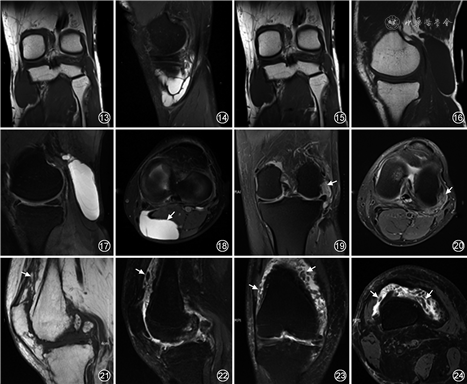

2.鹅足肌腱炎/滑囊炎综合征(pes anserinus tendino-bursitis syndrome,PATB):膝关节外翻、交叉韧带不稳、膝内侧骨质增生是PATB的危险因素。常见于骑马或摩托车职业运动员,因反复摩擦膝关节内侧而引起膝关节内侧疼痛,临床和影像学均难以明确肌腱炎、滑囊炎或者两者联合,因此统称为PATB。MRI显示鹅足滑囊积液肿胀(图13, 14, 15),需与半月板囊肿鉴别[1, 2, 3, 5, 6]。

4.腘窝囊肿:又称为Baker′s囊肿,其发病机制为关节疾病引起关节积液增多及液压增高,导致积液从薄弱的后关节囊处疝入腓肠肌内侧头-半膜肌滑囊,滑囊存在单向开放的瓣口,阻止液体反向流动,从而滑囊扩张积液。腘窝囊肿的发病率随年龄增长而增高,儿童罕见,最常见的症状是腘窝肿胀和后部疼痛,囊肿破裂可突发膝后部剧痛。MRI表现为腓肠肌内侧头前部和半膜肌之间边界清楚的液体聚集,呈“逗点状”,可观察到与膝关节腔相连(图16, 17, 18)。最常见的并发症是破裂和渗漏,其他并发症可包括腘动脉或神经的受压、感染或囊内出血,MRI信号可因感染、出血而表现复杂,囊内可出现分隔。鉴别诊断包括腘动脉瘤、软组织肿瘤、半月板囊肿、血肿、静脉血栓和血管瘤等[1, 2, 3, 8]。

2.树枝状脂肪瘤(lipoma arborescens,LA):是一种滑膜的绒毛状脂肪瘤样病变,又称为滑膜脂肪瘤病,通常累及膝关节髌上囊。LA的病因尚不清楚,多数学者认为本病并非真正的肿瘤,而是滑膜在多种因素作用下形成的非特异反应性增生病变,可以为特发性,也可继发于骨性关节炎、RA或创伤等。LA的病理特征是滑膜的绒毛状增生和成熟脂肪细胞广泛取代滑膜下组织。MRI是LA的主要诊断手段,在所有脉冲序列中呈滑膜树枝状增生伴有脂肪信号是最具有特征性(图21, 22, 23, 24)[20, 21]。